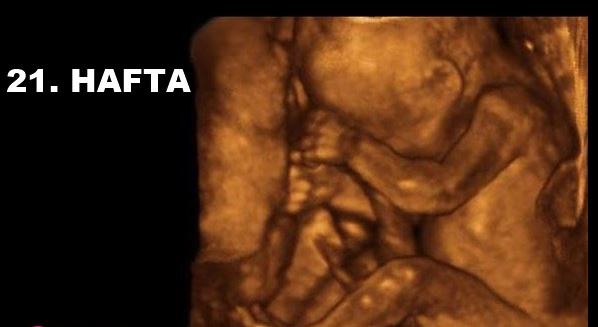

21 hafta ayrıntılı ultrason fotoğrafları

dr baris korkmaz